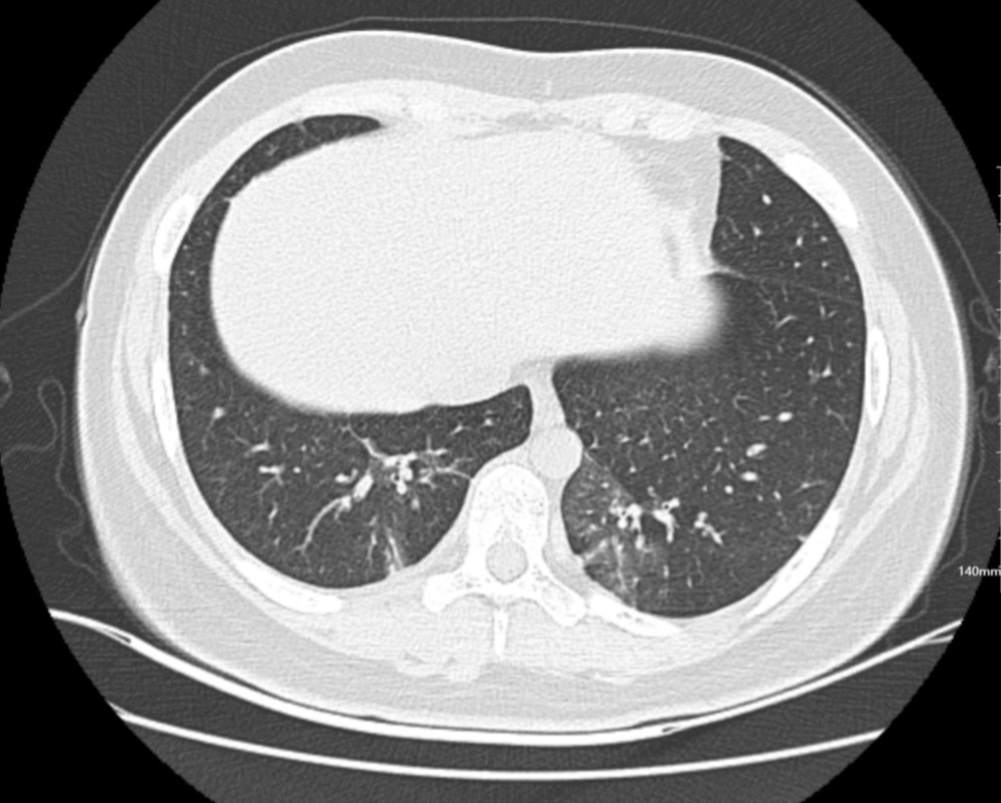

肺部CT:

百日咳肺炎CT 表现

支气管血管束增粗且伴 < 2 个肺叶的磨玻璃密度影, 多提示为单纯性百日咳肺炎。(下图:支气管血管束增粗, 两肺下叶基底段少许磨玻璃密度影)

如出现肺内支气管血管束增粗, 伴≥3 个肺叶斑片影、亚段性实变及支气管气象时, 提示患儿病情较重,可能合并其他感染。